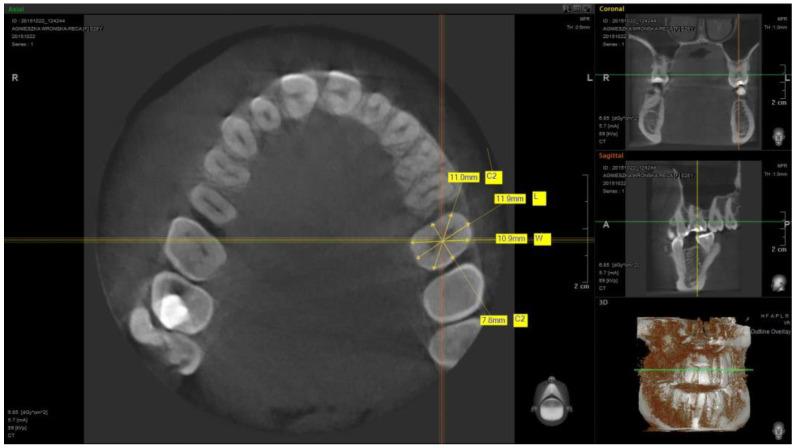

The study used cone-beam computer tomography (CBCT) scans of 51 patients. The measurements of the maxillary teeth (central incisor, lateral incisor, canine, first premolar, and first molar) were performed from cross-sections of the individual teeth at the transition zone to design a custom anatomic healing abutment milled from zirconium and luted to the non-index Ti-base.

本研究使用了51例患者的锥形束计算机断层扫描(CBCT)图像。从各颗牙齿在过渡区的横断面测量上颌牙齿(中切牙、侧切牙、尖牙、第一前磨牙和第一磨牙),以设计定制的解剖型愈合基台,该基台由锆铣削而成并粘结至非索引钛基台上。